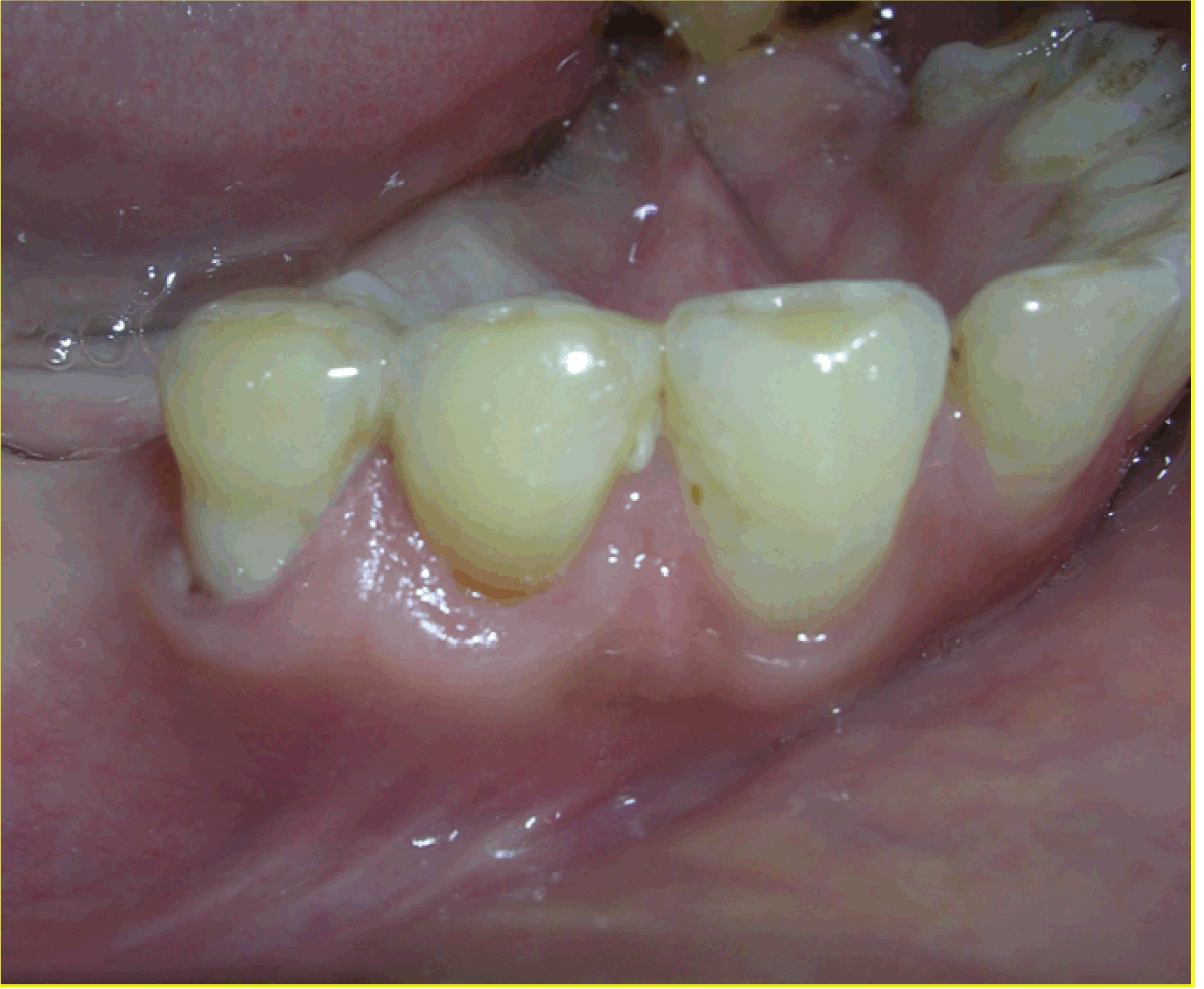

Case 3: A 35-year-old female patient presented and her main concern was the gums 'going down' in relation to the lower teeth on the left side. She was diagnosed as a case of Millers Class II recession in relation to 34 and 35 (Figure 6). This case too was treated using the pouch and tunnel technique with placement of CTG procured from the palate. The donor site appeared normal in color and healthy after four weeks and the recipient site was healthy with excellent color match with adjacent tissues in all four cases. These results were stable and maintained at the time of review, 12 months in Case 1 (Figure 7), 18 months in Case 2 (Figure 8), six months in Case 3 (Figure 9). The mean root coverage achieved in these cases was an average 90% which is close to the mean root coverage of 91.6% in the Zabaluigi study.

Figure 6: Millers Class II recession on 34 and 35.

Figure 9: Postoperative image after six months (Case 3).